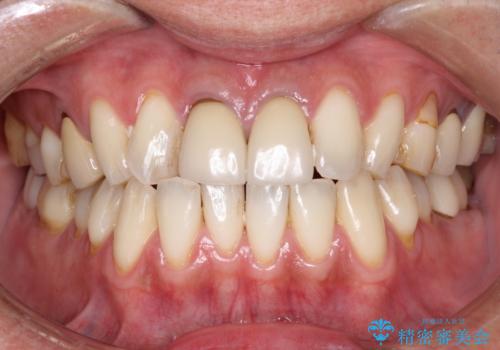

タバコによるヤニをPMTC(歯科医院での専門的クリーニング)で除去。

担当医 歯科衛生士